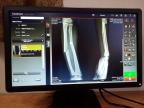

A Carestream Vita Flex CR system in Kunde, Nepal, provides imaging services for residents, mountaineers, sherpas and others who support expeditions to Mount Everest (Photo: Business Wire)

The Carestream Vita Flex CR system is used by medical staff to capture digital X-ray images of shoulders and extremities that have been broken or sprained; the head and neck area to diagnose sprains or concussions; as well as chest exams that may indicate a patient has pneumonia, altitude sickness, or evidence of a heart attack or other serious medical conditions.

“These imaging studies are essential to diagnosing diseases and injuries to climbers, sherpas and other workers at base camp. The images are available in minutes and physicians decide if a patient can be treated at the hospital or must be transported to Kathmandu by helicopter or airplane,” said Charlie Hicks, Carestream’s General Manager of Global X-ray Solutions.

A Carestream Vita Flex CR system captures digital X-ray images that help physicians detect diseases and injuries suffered by climbers and support staff for Mount Everest expeditions (Photo: Business Wire)